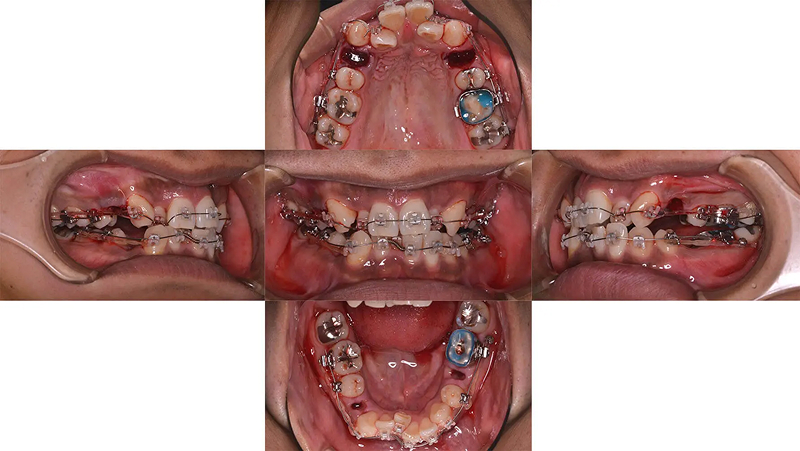

Case02前歯の凸凹を改善した症例

前歯の凸凹が著しい状態でした。清掃がしにくく、上顎側切歯がロックされていました。むし歯治療とともに矯正治療をすることになりました。診査の結果、歯列にスペースがないことがわかりました。口元をきれいにし、歯列を整えるには小臼歯4本抜歯が必要と診断しました。仕事をしながらなので、通院が少し大変でしたが、無事きれいな歯列を獲得できました。

初診 2014.10.16

矯正治療開始 2014.11.26

矯正治療終了 2016.7.12

ファイナル 2016.12.22

治療後2年半 2019.6.24

| 主訴 | 前歯の凸凹を治したい |

|---|---|

| 診断 | 両側アングル1級の叢生 |

| 矯正方法 | 小臼歯4本抜歯を伴うマルチブラケット |

| 矯正期間 | 20か月・21回 |

| 費用 | 746,000円(税別) |

| 調整料 | 月1回 5,000円(税別) |